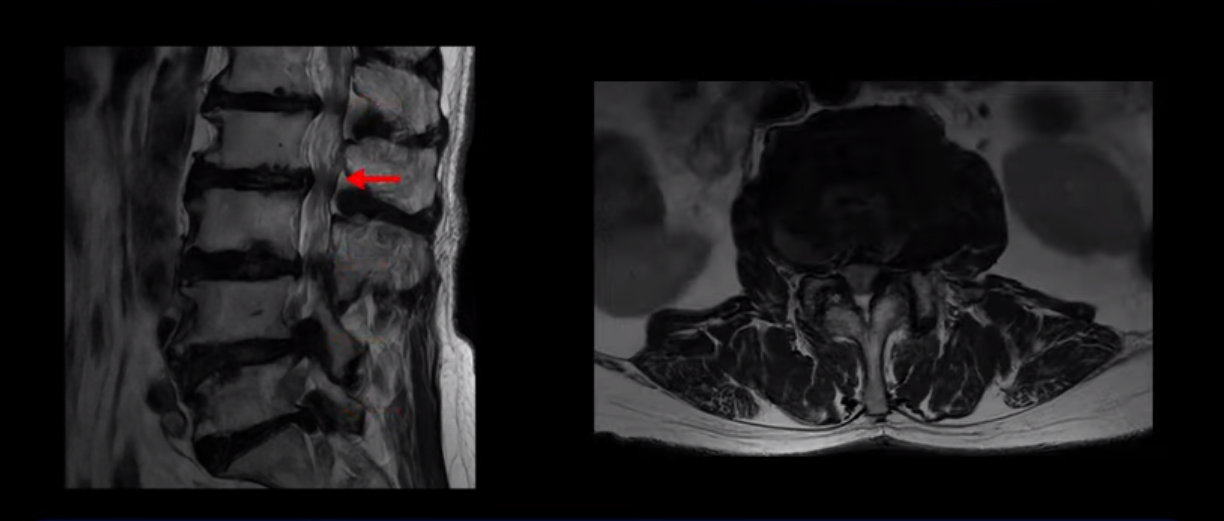

MRI 보시면 (2-8) 허리의 5마디가 전부 다 심하게 퇴행되어 있습니다.

5마디 전부 다 심한 중심성 협착이 있습니다.

2번 3번,

3번 4번,

이렇게 모두 다 심하게 막히는 경우는 드문데요. 또한 오른쪽, 왼쪽 신경이 빠져나가는 추간공도 다 심하게 막혀있습니다.

오른쪽, 왼쪽 이렇게 신경 구멍들이 다 좁아지고 신경이 눌리니까 양쪽 다리가 발바닥까지 아파서 걷기 어렵고 양쪽 발이 10년 넘게 시린 겁니다. 당연히 수술해서 눌린 신경을 풀어줘야 한다고 들으셨는데요. 이런 환자분을 어떻게 수술 없이 치료할까요? 지금부터 설명해 드립니다.

이분 신경이 눌리는 증상은 오래됐지만, 증상이 아주 심해진 건 올해 들어와서입니다. 그럼, 이분 MRI 영상도 이렇게 심하게 안 좋아진 게 올해 들어와서일까요? 이분의 MRI로 보이는 협착은 아주 오래된 겁니다. 그래서 신경 구멍이 심하게 좁아진 것도 올해가 아니고 오래된 겁니다. 작년, 재작년에 훨씬 덜 아팠을 때 MRI를 찍었어도 신경 구멍 좁은 정도는 별반 차이가 없었을 겁니다.

실제로 수많은 논문에서 70세 이후 MRI로 협착이 보여도 아프지 않은 무증상 협착이 많다고 설명합니다. 협착이 있어도 안 아픈 사람들이 많다는데, 이게 왜 그럴까요? 근육 기능이 정상적이고 좋은 사람들은 근육이 허리를 잘 지지해 주니까 협착이 있어도 신경이 덜 눌리거나 안 눌리는 겁니다. 즉 근육이 좋으면 신경이 덜 눌리고 근육이 좋아지면 협착증이 좋아지는 겁니다. 그래서 저희가 근육 재활치료를 통해 근육의 기능을 회복시키면서 동시에 신경의 기능을 회복시키는 치료를 하는 겁니다. 이런 분들이 근육 재활치료를 통해서 협착증 증상이 좋아진다면 이런 분들의 협착증도 아프지 않은 무증상 협착으로 바뀌게 되는 겁니다.